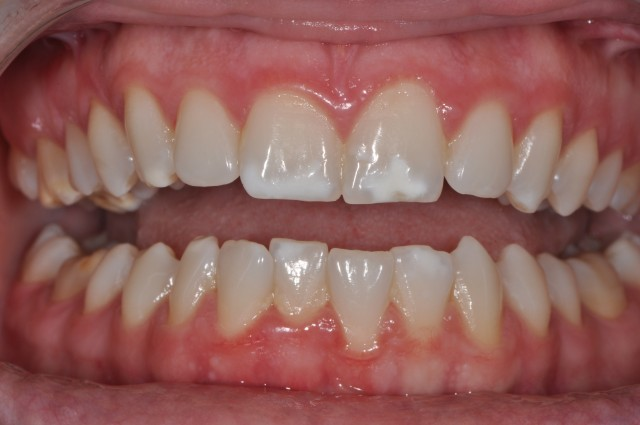

Another application for MI Paste Plus is the elimination of white spot lesions. WSLs are areas of opacity or hypocalcified enamel on the clinical crown, caused by incipient carious lesions secondary to the plaque buildup. This increase in plaque creates an acidic environment that ultimately leads to the demineralization of tooth structure.

WSLs are commonly seen around orthodontic brackets and bands in patients with poor oral hygiene. These areas can then become demineralized. As a result, the enamel surface of the tooth exhibits a milky or chalky white opacity that becomes very unaesthetic. Patients, in turn, can lose confidence in their appearance.

With the advent of MI Paste Plus, it’s possible to treat these areas before bleaching, significantly improving a patient’s smile. Applying MI Paste Plus to the tooth can remineralize the tooth surface, making whitening more successful and resulting in a more symmetric and esthetic tooth appearance.